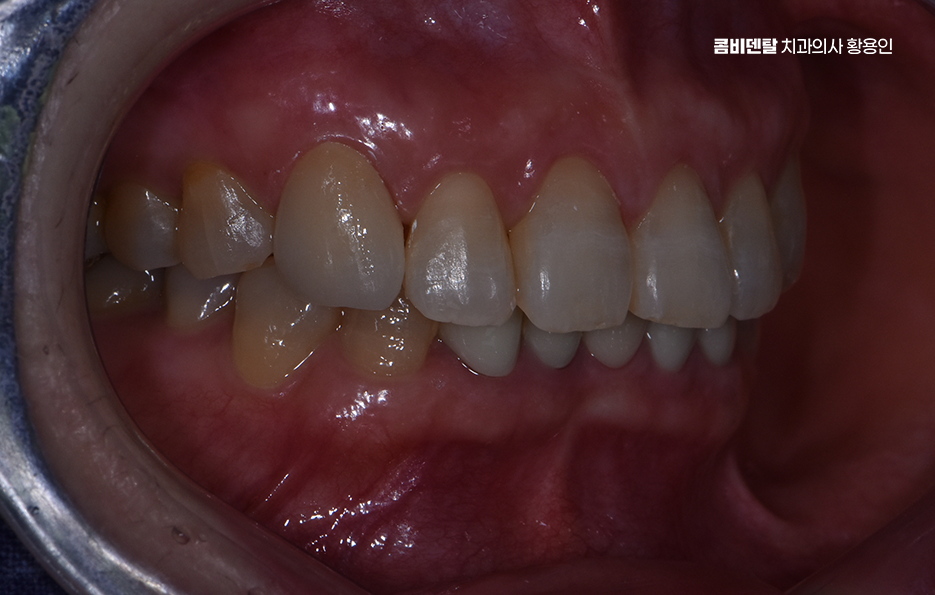

다만 남아있는 잔존 치아가 부족한 경우에는 내구성도 중요하기 때문에 내구성이 높은 지르코니아를 선택하게 되는 경우도 많고 요즘은 올세라믹과 지르코니아의 장점을 합친 하이브리드 올세라믹 크라운의 선택도 점점 많아지고 있었어요

그리고 물론 치료 과정도 중요한데 아무리 좋은 재료를 써도, 본을 잘못 뜨거나 치아 삭제량이 과하면 치아의 수명도 더 줄어들 수 밖에 없고 결과가 자연스럽지 않을 수 있으며 송곳니는 치근이 길고, 뿌리 방향이 독특한 구조를 가지고 있기 때문에 섬세하고 정교한 치료가 중요하기 때문에 경험 많은 치과의사와 함께 하는 것도 중요한 부분이라 할 수 있었어요

마지막으로 송곳니 크라운 치료를 고려할 때 장기적인 안정성과 수명 유지에 대해서도 고려해야 하는데 세라믹 계열의 크라운은 내구성이 높긴 하지만 깨질 우려에 대해 주의해야 하며 보통 크라운은 10년 정도를 수명으로 예상하지만 개인의 관리에 따라 더 짧아지기도 하고 길어지기도 하므로 정기적인 검진을 통해 보철물 수명을 잘 관리하는 것이 곧 자연치아의 수명과도 직결된다는 점을 잘 이해하시고 실천하시길 바라고 있었어요

정리하면 송곳니 크라운 치료를 고민하신다면 사람과 대화하고, 웃고, 감정을 표현할 때 자연스럽게 드러나는 치아이기 때문에 더욱 완성도 높은 치료가 필요하고 치료 자체도 중요하지만 크라운을 씌울 정도로 자연치아의 손상이 이미 발생 했다면 더 추가적인 문제가 진행되지 않도록 꼭 원인 파악과 재발 방지에 힘쓰시길 바라고 있어요